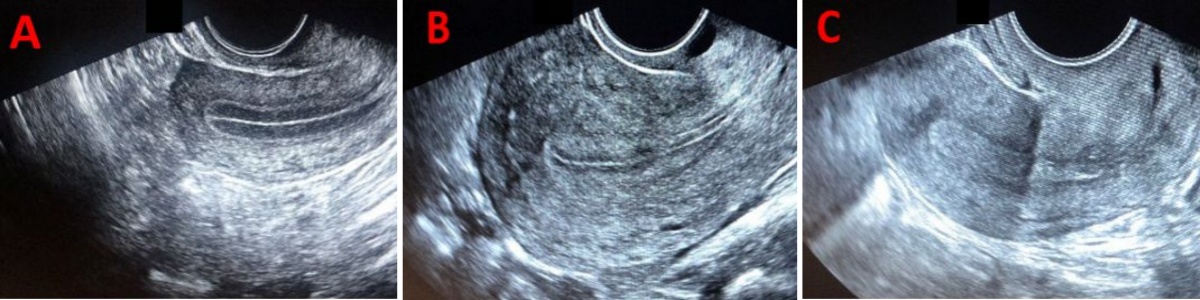

除厚度外,内膜形态和血流灌注是评估内膜容受性的两个重要补充指标。内膜形态可依据超声下内膜与肌层的回声对比分为三型:A型内膜呈现清晰的三线征,提示内膜处于适宜的增殖期或分泌早期转化状态;B型内膜三线征模糊;C型内膜为均匀高回声,通常提示内膜转化过度或分泌晚期改变。一般来说,移植日呈现A型内膜的女性,其妊娠率高于B型或C型者。